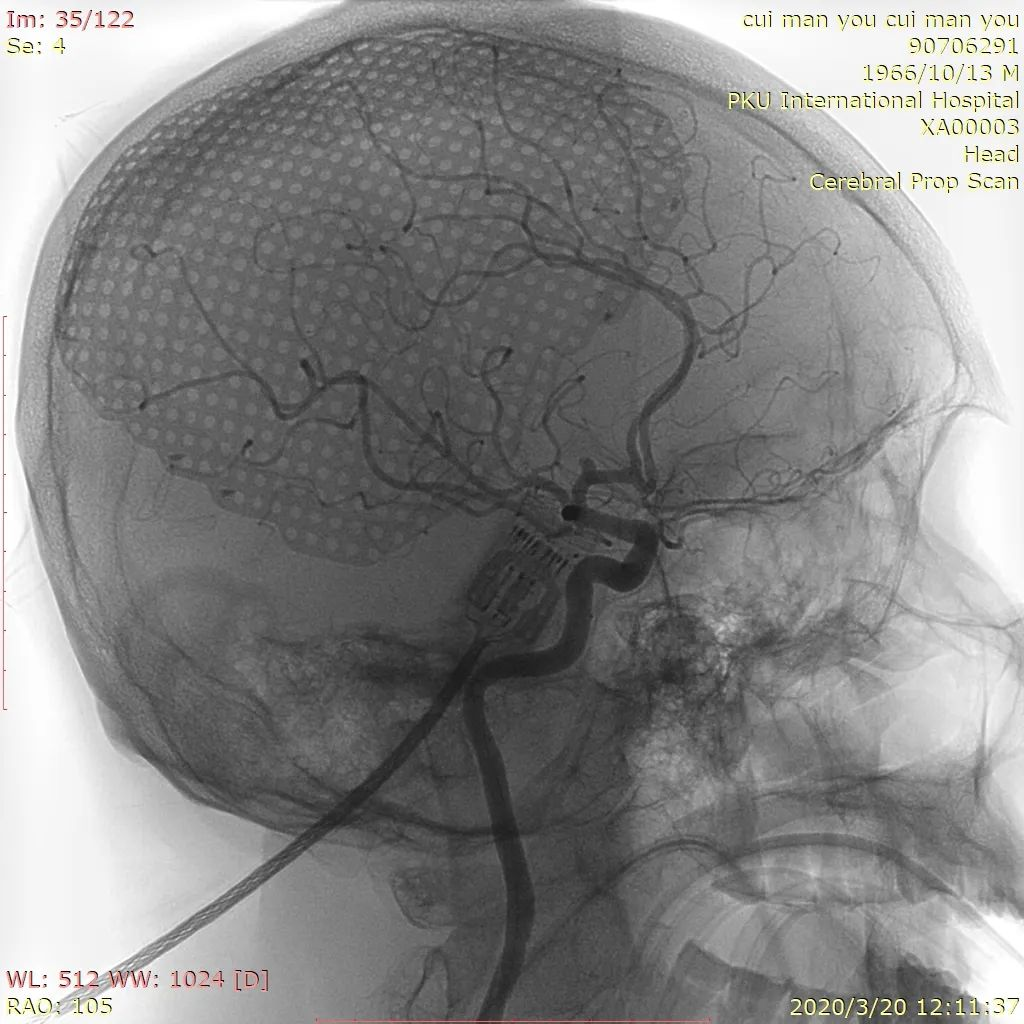

图5 Lvis支架释放